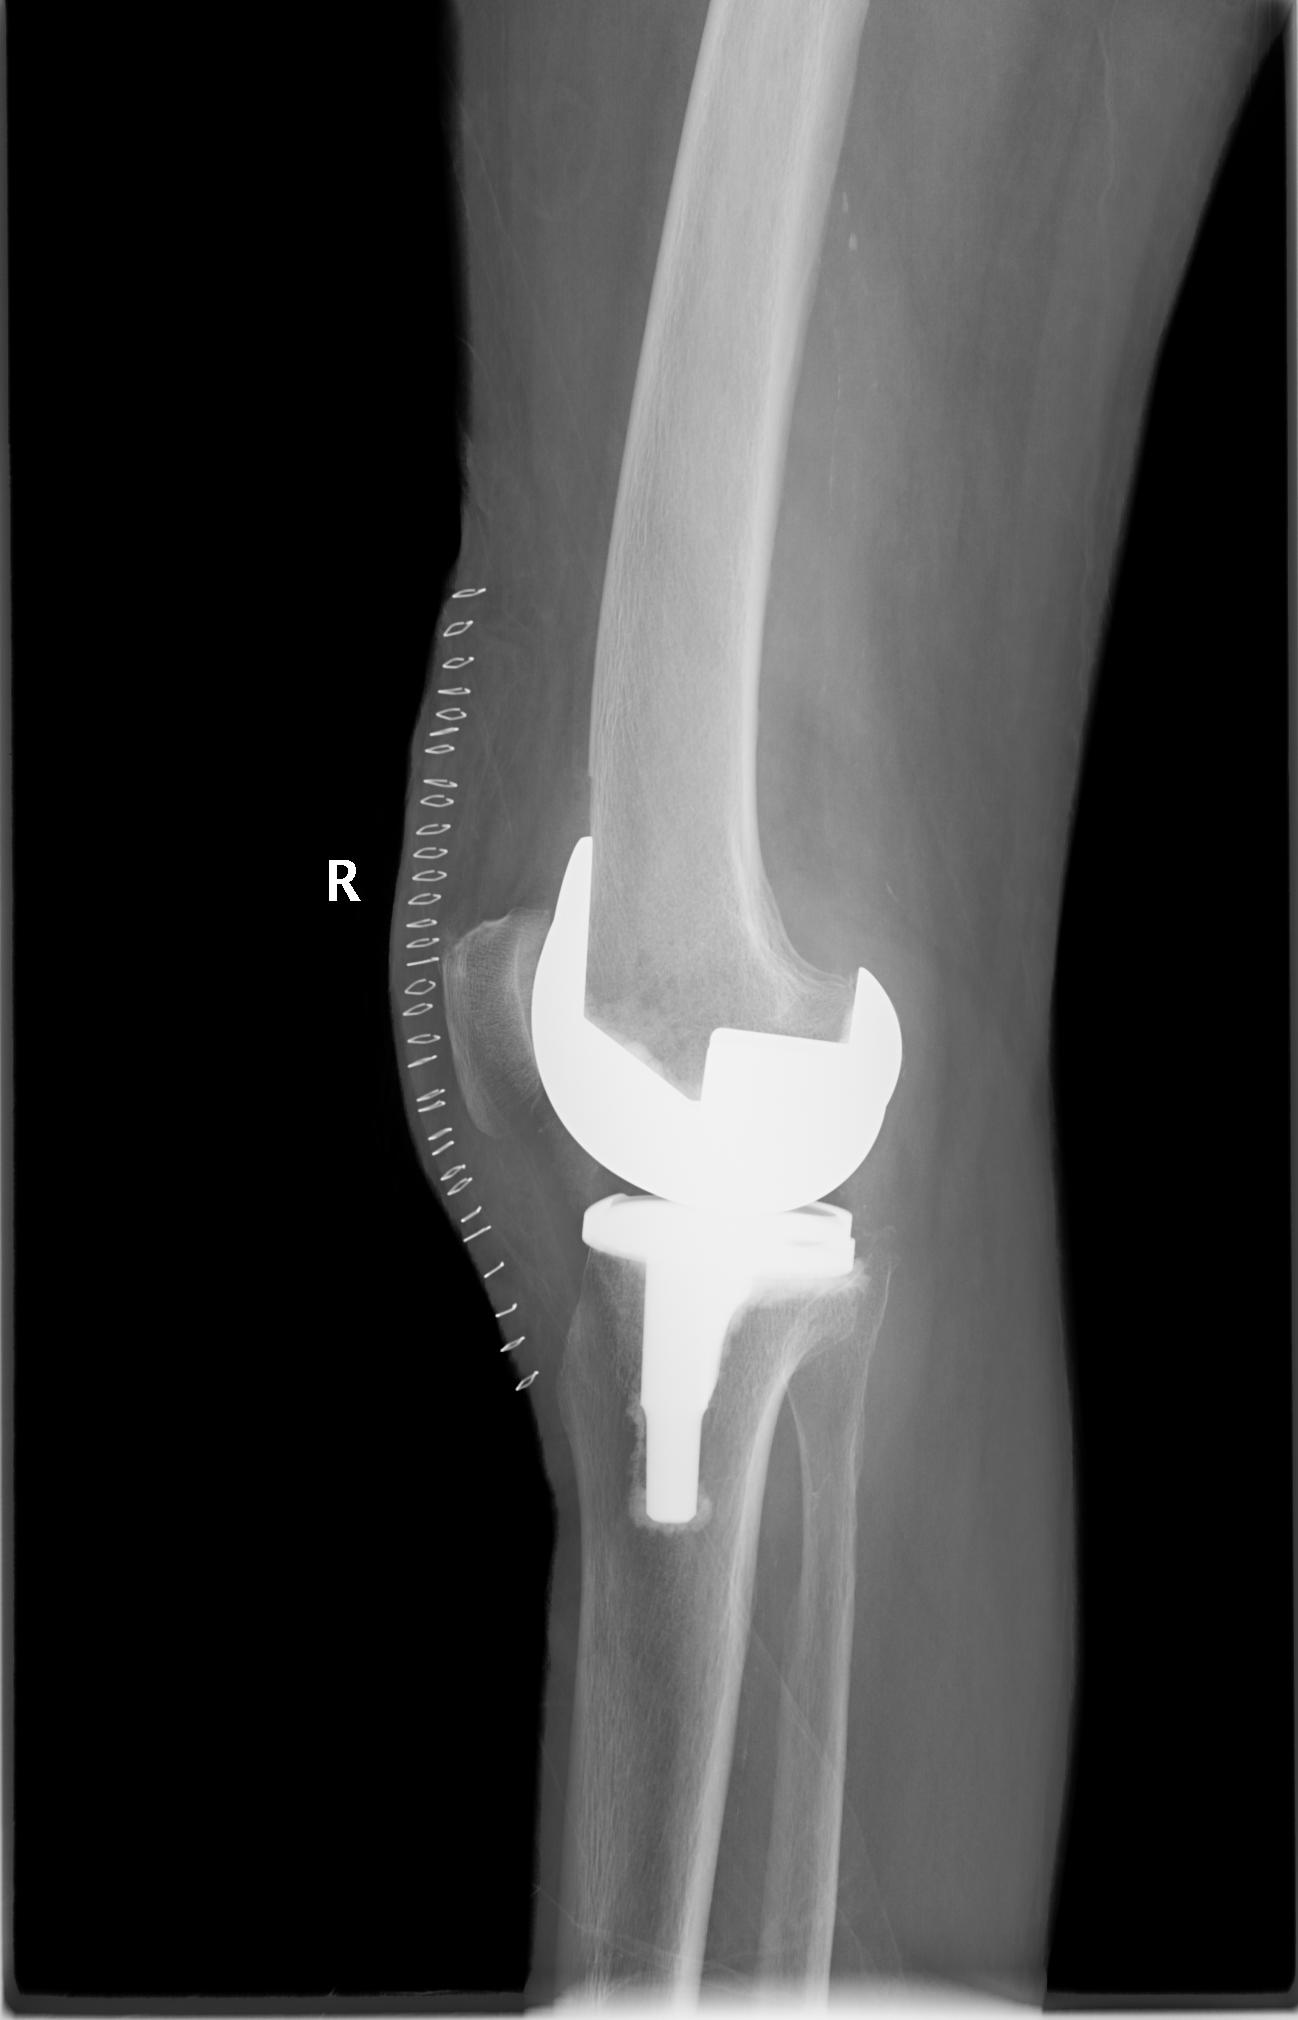

病例二:患者女性,82歲。主因“右膝疼痛10年伴加重、活動(dòng)受限半個(gè)月”入院。入院前右膝痛時(shí)好時(shí)壞,疼痛劇烈時(shí)無法站立。

患者術(shù)前全長

患者術(shù)后

患者術(shù)后全長